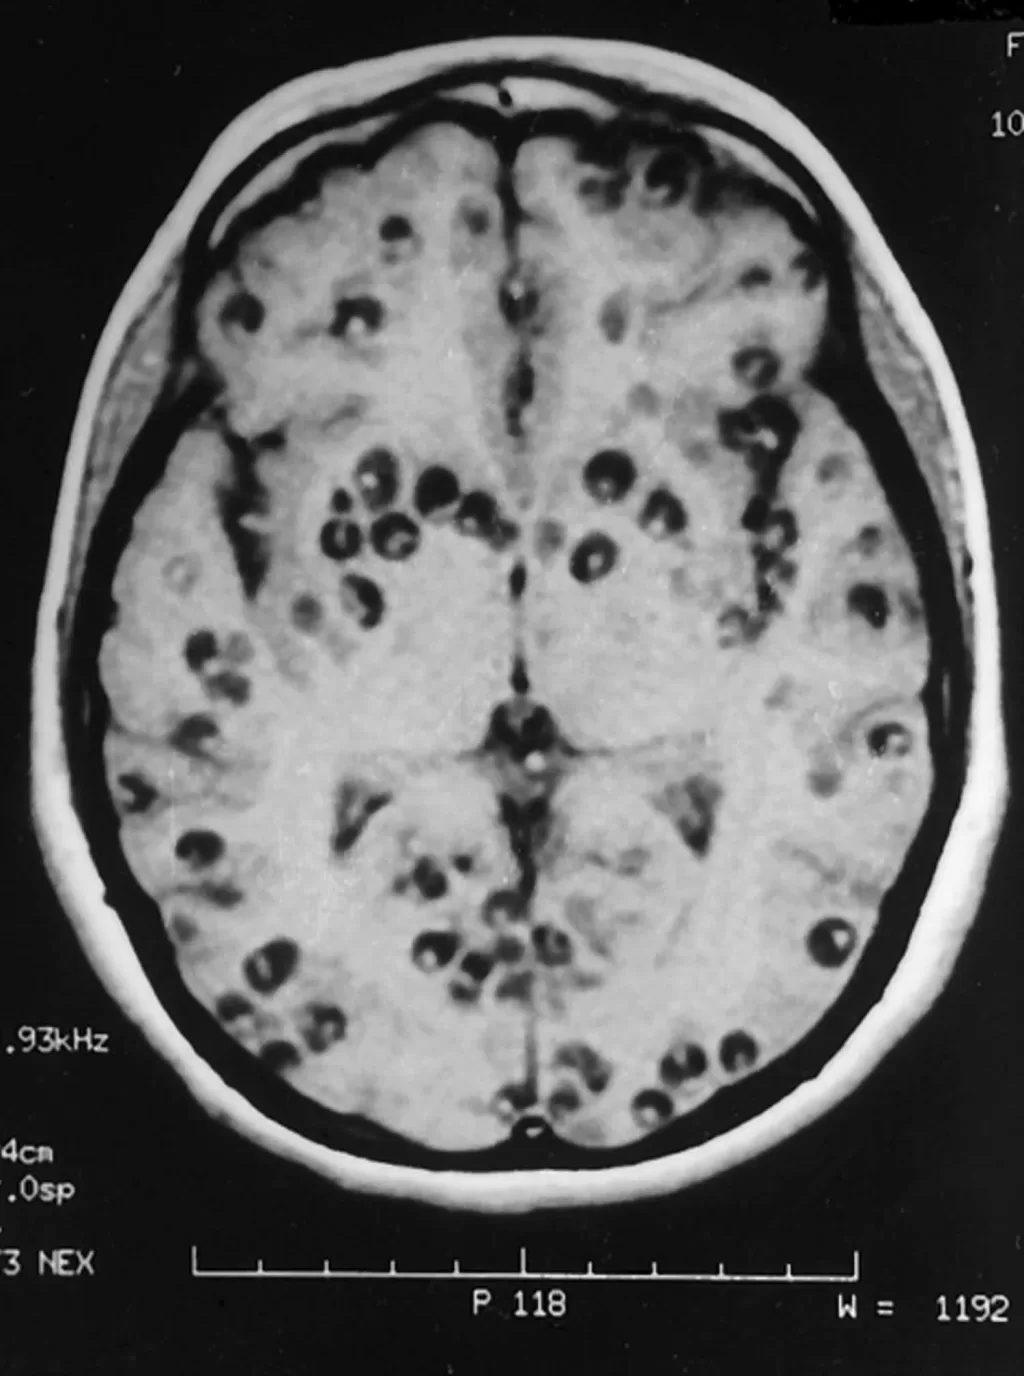

Patients with neurocysticercosis may exhibit a range of symptoms, including seizures, headaches, and cognitive impairment, which can drastically affect their quality of life. Diagnosing the condition can be challenging, often requiring advanced imaging techniques such as MRI, serological tests, and in some cases, molecular methods for confirmation. Early identification and treatment are crucial in preventing severe complications.

Diagnosing neurocysticercosis can be fraught with challenges due to the variable presentations and the potential for overlap with other neurological diseases. Identification often relies on imaging techniques like MRI, which can reveal cyst-like lesions in the brain. However, the presence of *T. crassiceps* may not always produce typical imaging findings, complicating diagnosis.

| MRI Findings | Enlarged ventricular system indicating subarachnoid neurocysticercosis. |